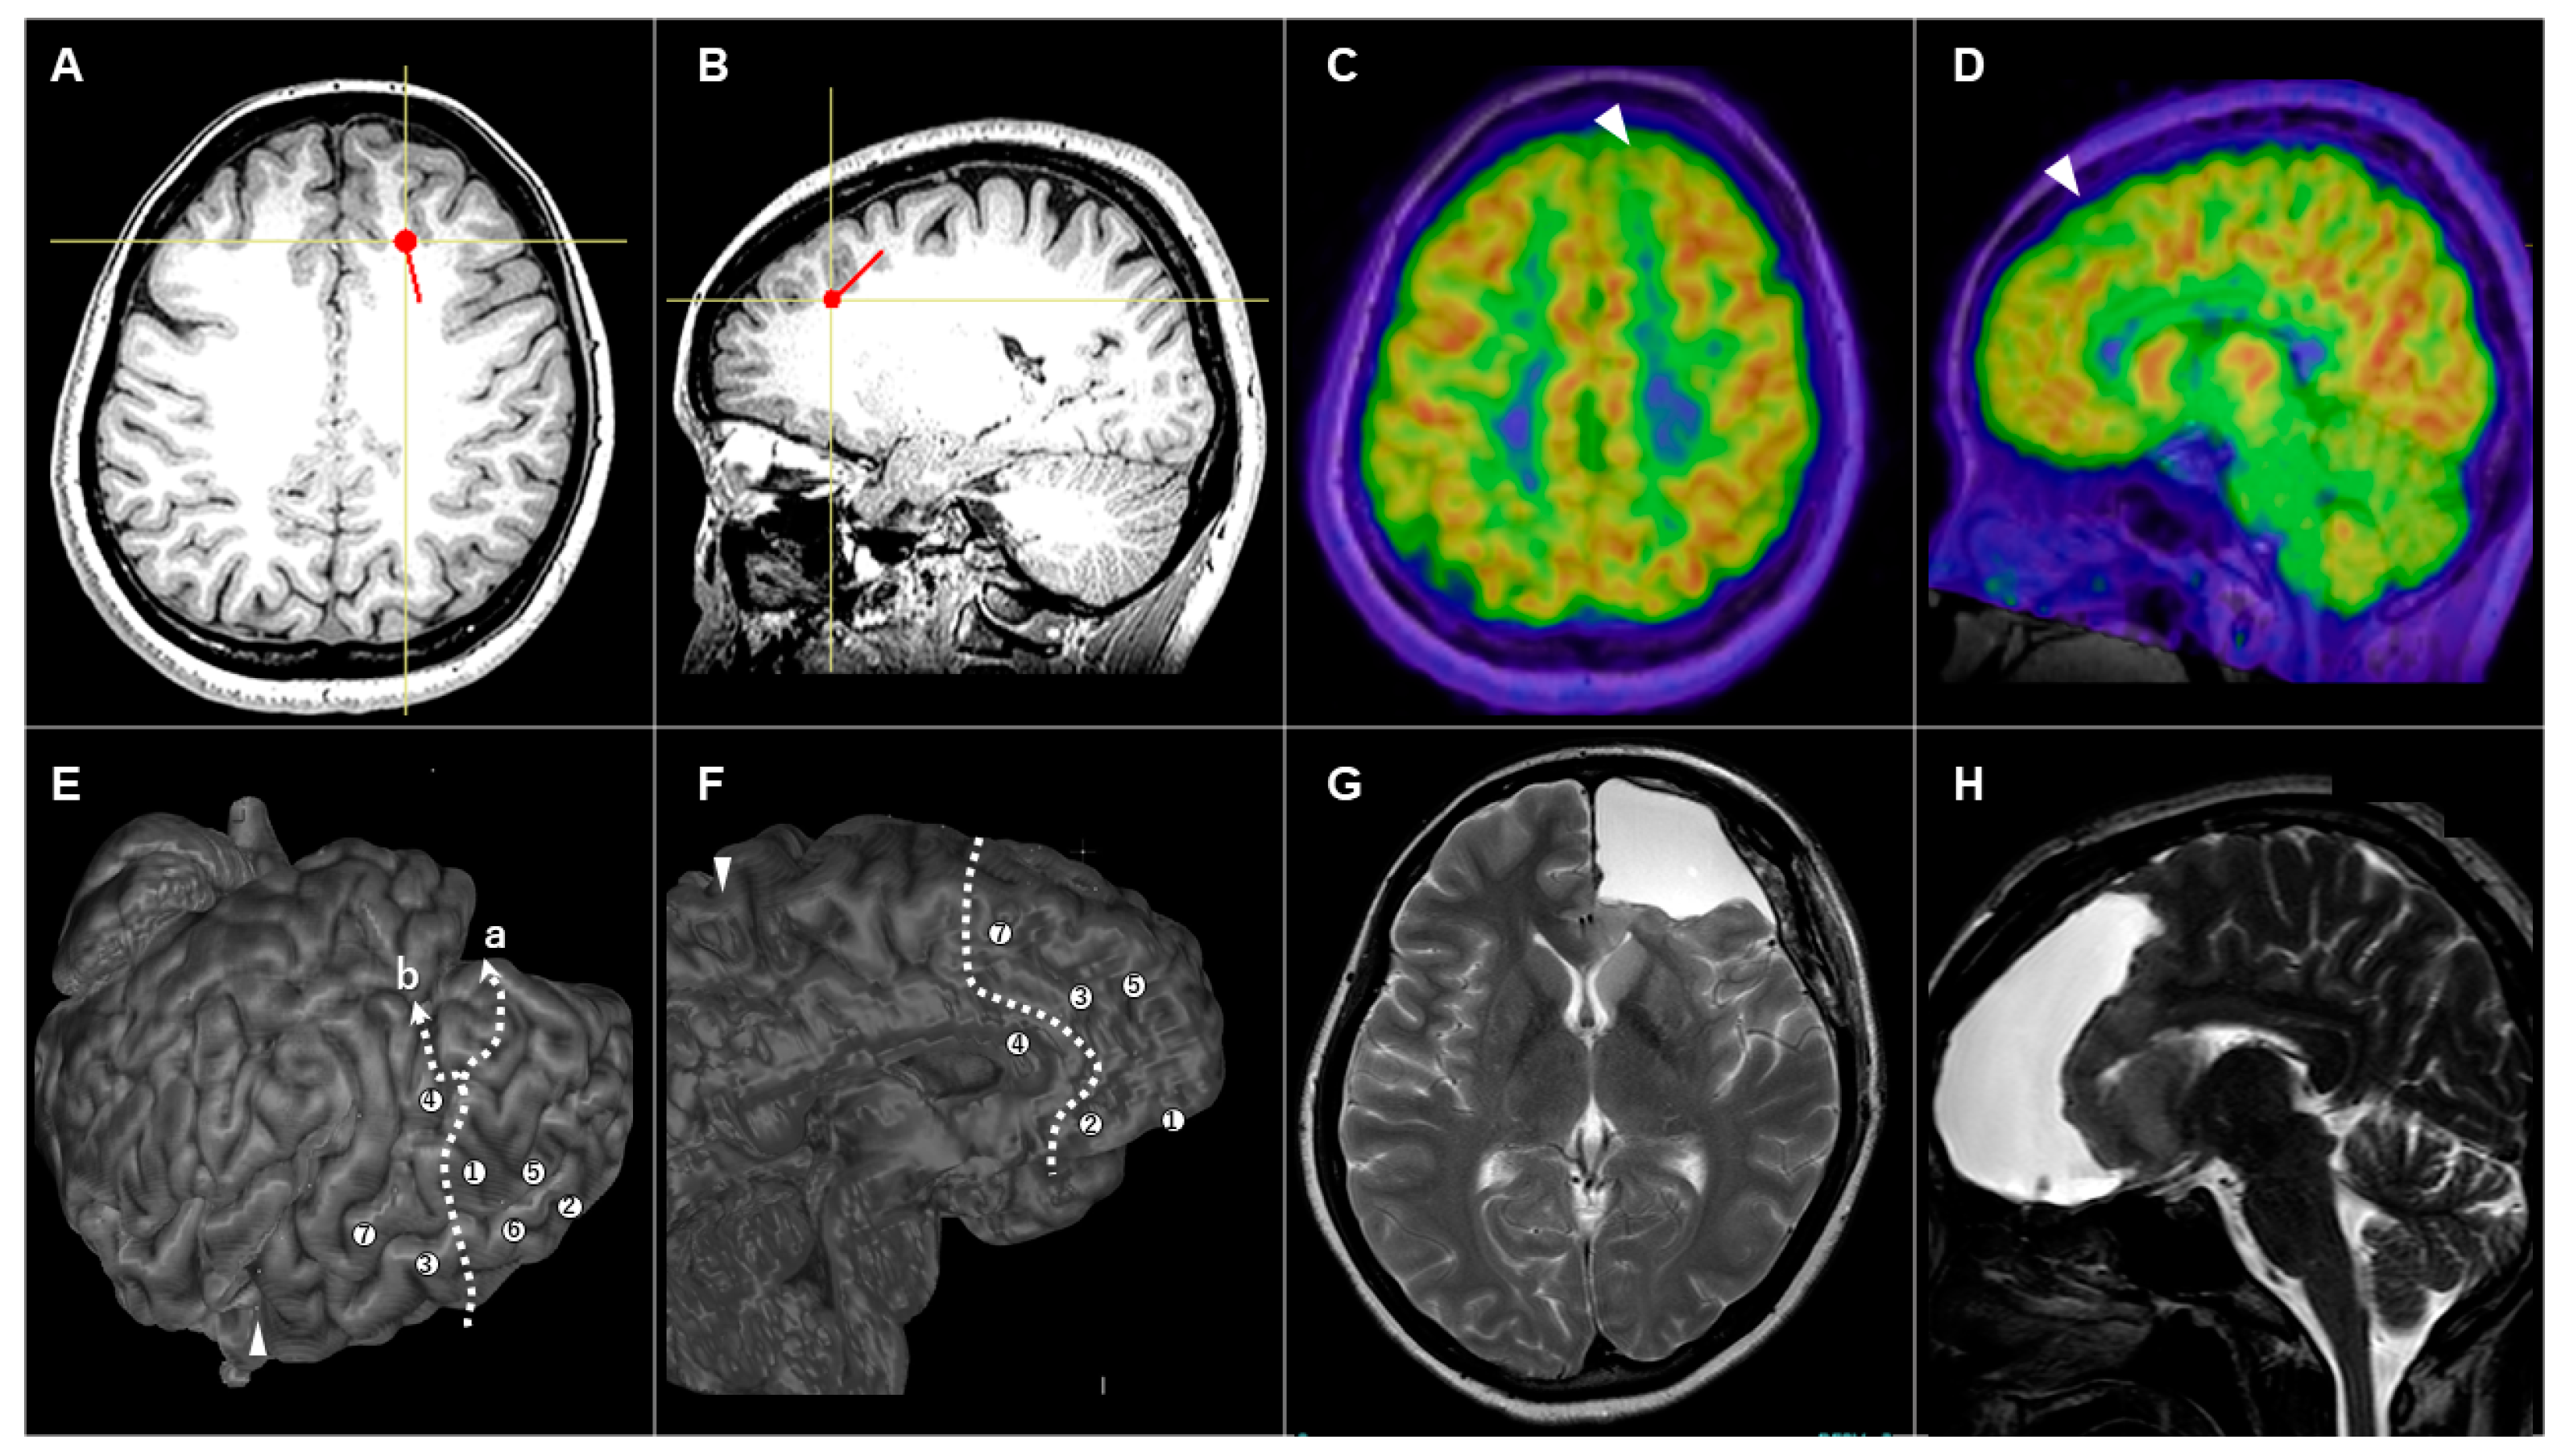

3.3.1. Patient #1 (AWC#1) (Figure 2)